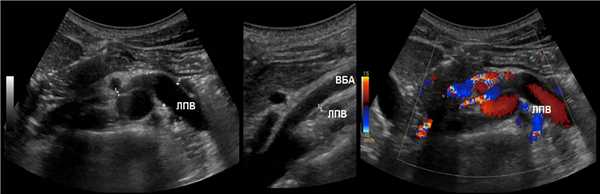

ППА проходит позади нижней полой вены. ЛПВ проходит через «пинцет» между аортой и верхней брыжеечной артерией. Иногда встречается кольцевидная ЛПВ, тогда одна ветвь располагается впереди, а другая — позади аорты.

Рисунок. Почечные вены впадают в нижнюю полую вену (1, 2). Аортомезентериальный «пинцет» может сдавливать ЛПВ (3).

Доплер почечных вен

Левая почечная вена проходит между аортой и верхней брыжеечной артерией. Аортомезентериальный «пинцет» может сдавливать вену, что ведет к венной почечной гипертензии. В положении стоя «пинцет» сжимается, а в положении лежа — раскрывается. При синдроме Щелкунчика затрудняется отток по левой яичковой вене. Это фактор риска развития левостороннего варикоцеле.

Из-за сдавления спектр ЛПВ похож на воротную вену — спектр выше базовой линии, постоянная низкая скорость, контур плавными волнами. Если соотношение диаметра ЛПВ перед и в зоне сужения более 5 или скорость потока менее 10 см/сек выносим заключение о повышении венозного давления в левой почке.